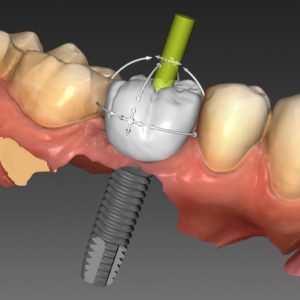

IMPLANTÁTY

Zubní implantát často považujeme jako první volbu pro náhradu ztraceného zubu. Prošly úžasným vývojem umožňují nahradit jeden až všechny zuby.

Zubní implantát často považujeme jako první volbu pro náhradu ztraceného zubu. Prošly úžasným vývojem umožňují nahradit jeden až všechny zuby.